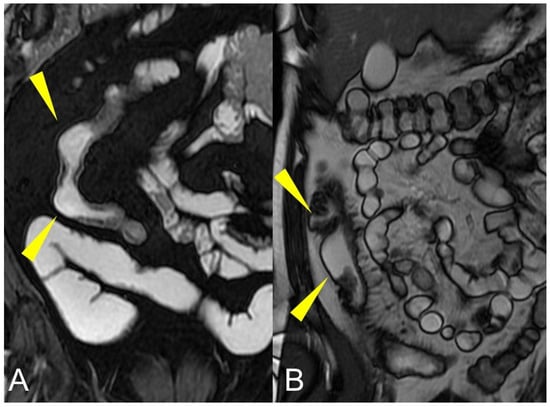

Thickening throughout the intestinal loop circumference might be eccentric (asymmetric) or circumferential (symmetric) depending on the type of involvement (Figure 16B,C) [29,30]. According to the length of the pathological bowel tract, thickening can be focal, segmental, or diffuse. Bowel thickening is defined as focal when the pathological tract is shorter than 5 cm in length (Figure 17A); segmental thickening refers to 6–40 cm in length of thickened small bowel (Figure 17B), while it is considered diffuse when a large amount of small bowel loops (>40 cm) is affected (Figure 17C) [29,30]. After contrast-medium injection, various patterns of wall enhancement can be described: stratified, white, and gray [30]. Contrast enhancement is classified as stratified when there is hyperintensity of the inner layer (muco-sa), hypointensity of the intermediate layer (submucosa), and hyperintensity of the outer layer (muscle and serosa layers); this is caused by mucosal hyperemia and submucosal edema. If stratified contrast enhancement is associated to fat deposits in the submucosal layer, it is called “fatty halo” sign [30,31].

Figure 17.

Focal, segmental, or diffuse thickening. (A) Axial T1-weighted after gadolinium injection image shows focal thickening of the distal ileum, shorter than 5 cm in length (arrow), with avid contrast enhancement. (B) Coronal T1-weighted after gadolinium injection image shows segmental thickening of an ileal loop in the pelvis, with 6–40 cm in length (arrow). (C) Axial T1-weighted after gadolinium injection image shows diffuse thickening of a large amount of small bowel loops (>40 cm) (arrows).